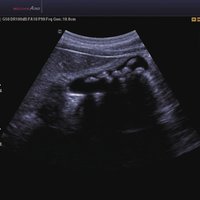

Das Samsung Accuvix A30 ist ein hochwertiges Ultraschallsystem, das mit seiner 3D-Technologie herausragende Ergebnisse ermöglicht. Das Sonographiegerät besitzt 5 Sondenanschlüsse und ist mit 20 unterschiedlichen Schallköpfen kompatibel. Mit dem A30 können Schallköpfe vom Typ Konvex, Mikrokonvex, 3D-Konvex, CW, Phased Array, Linear und Endokavitär verwendet werden. Bei zwei der Sonden handelt es sich um S-VUE Ultraschallsonden, die durch ihre höhere Bandbreite noch feinere Scans erzeugen.

Das Ultraschallsystem hebt sich besonders durch seine 3D-Technologie wie die Face Auto Detection für detaillierte Ultraschallbilder von Föten oder das Volume Shade Imaging, das sich auf die lebensnahe Darstellung von Schattierungen und Hauttönen fokussiert, ab. Mit weiteren wertvollen Technologien wie dem ElastoScan™ werden Tumore schneller erfasst und durch die HD Volumen Bildgebung sowie das DMR+™ eine erstklassige Bildqualität erzielt.